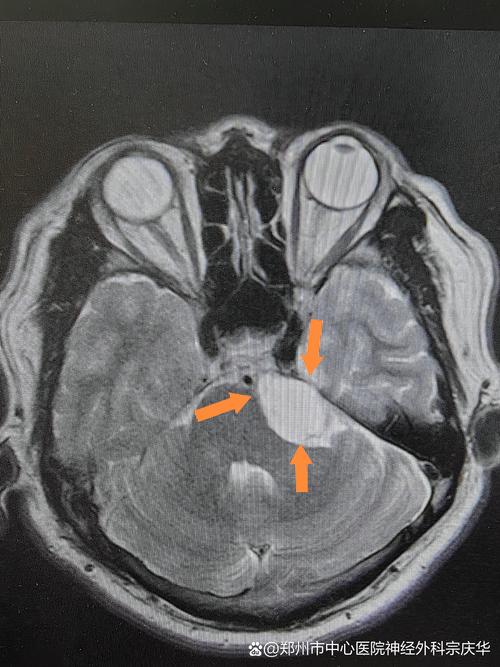

- 弥散加权成像 (DWI) 和 表观弥散系数 (ADC):

- 对急性脑脓肿的诊断有“决定性”意义,脓肿的中心区域由于细胞密集,水分子运动受限,在DWI上呈高信号,而肿瘤的坏死区通常呈低信号。

| 脑脓肿 | 低信号 | 高信号 | 环形强化 | 中心极高信号 (特征性) |